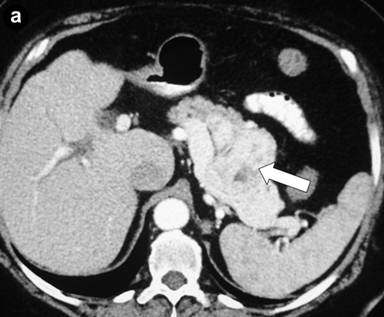

Postoperative histological examination of the resected specimen or taken biopsies revealed pancreatic metastases of extrapancreatic malignomas (Figure 1) in 8 patients (renal cell carcinoma, n=3; melanoma, n=2; duodenal gastrinoma, n=1; breast cancer, n=1; retroperitoneal liposarcoma, n=1). In 10 patients (52.6%) the following rare benign tumors were detected: solid pseudopapillary tumor of the pancreas (n=3) (Figure 2), mature teratoma of the pancreas (n=2) (Figure 3), capillary hemangioma of the pancreas (n=1) (Figure 4), intrapancreatic accessory spleen (n=1) (Figure 5), lymphoepithelial cyst of the pancreas (n=1) (Figure 6), hamartoma of the pancreas (n=1) (Figure 7), and pancreatic sarcoidosis (n=1). In one patient an advanced yolk sac tumor of the pancreas with peritoneal carcinosis was diagnosed (Table 2).

Figure 1. Intrapancreatic metastasis of a renal cell carcinoma (arrow). a. Preoperative CT scan. b. Histology of a pancreatic metastasis of a renal clear cell carcinoma (G2); tumor cell clusters (arrow), pancreatic parenchyma with chronic inflammation on the right (H&E-staining). |